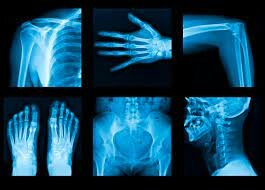

• Estructura del tubo de rayos x

Estructura del tubo de rayos x

• RAYOS X -Tubo De Coolidge

RAYOS X -Tubo De Coolidge

Este tubo brinda una marcha estable, regular, uniforme, de fácil manejo en la ejecución de diferentes técnicas de exploración radiológica a la que se agregó la naturaleza rotatorio del ánodo, la creación del anti difusor secundario Poterbucky, la estandarización de la radioscopia, la creación del serio grafo, el perfeccionamiento de los chasis con pantalla reforzadora, el perfeccionamiento de películas radiográficas, la creación de diafragmas, conos, filtros, desarrollo de los métodos.